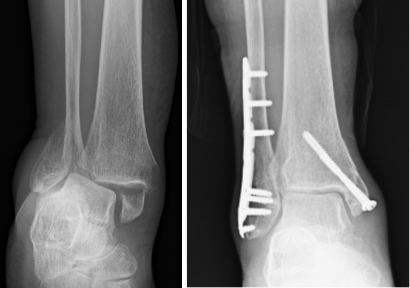

■骨接合術